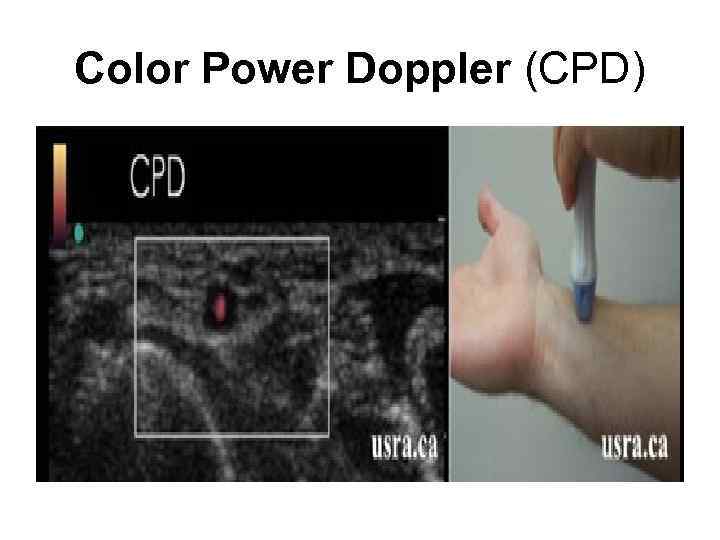

Color Power Doppler (CPD)

Color Power Doppler (CPD)

Энергетический допплер • качественная оценка низкоскоростного кровотока, применяется при исследовании сети мелких сосудов (щитовидная железа, почки, яичник), вен (печень, яички) и др. • Более чувствителен к наличию кровотока, чем цветовой допплер.

Энергетический допплер • качественная оценка низкоскоростного кровотока, применяется при исследовании сети мелких сосудов (щитовидная железа, почки, яичник), вен (печень, яички) и др. • Более чувствителен к наличию кровотока, чем цветовой допплер.

Энергетический допплер На эхограмме обычно отображается в оранжевой палитре, более яркие оттенки свидетельствуют о большей скорости кровотока.

Энергетический допплер На эхограмме обычно отображается в оранжевой палитре, более яркие оттенки свидетельствуют о большей скорости кровотока.

Энергетический допплер • Главный недостаток - остутствие информации о направлении кровотока.

Энергетический допплер • Главный недостаток - остутствие информации о направлении кровотока.

Энергетический допплер Использование энергетического допплера в трехмерном режиме позволяет судить о пространственной структуре кровотока в области сканирования.

Энергетический допплер Использование энергетического допплера в трехмерном режиме позволяет судить о пространственной структуре кровотока в области сканирования.

Энергетический допплер - power doppler • В эхокардиографии энергетический допплер применяется редко, иногда используется в сочетании с контрастными веществами для изучения перфузии миокарда. • Цветовой и энергетический допплер помогают в дифференциации кист и опухолей, поскольку внутреннее содержимое кисты лишено сосудов и, следовательно, никогда не может иметь цветовых локусов.

Энергетический допплер - power doppler • В эхокардиографии энергетический допплер применяется редко, иногда используется в сочетании с контрастными веществами для изучения перфузии миокарда. • Цветовой и энергетический допплер помогают в дифференциации кист и опухолей, поскольку внутреннее содержимое кисты лишено сосудов и, следовательно, никогда не может иметь цветовых локусов.